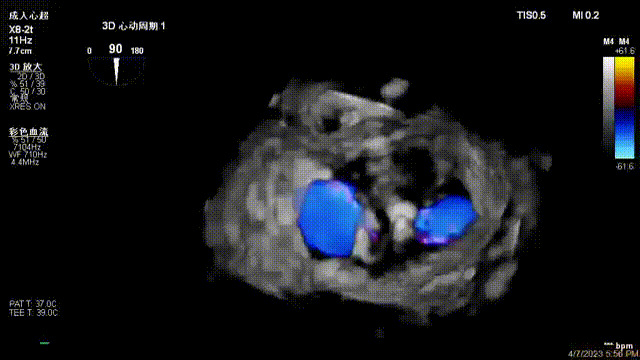

出院前隨訪超聲

接受治療的是一例器質(zhì)性重度二尖瓣反流(DMR)患者,主訴“反復(fù)活動后胸悶,氣促3年余”。術(shù)前超聲顯示,雙房增大,二尖瓣脫垂伴重度反流,輕度三尖瓣反流,輕度肺高壓,升主動脈增寬。手術(shù)經(jīng)股靜脈-房間隔入路,采用全身麻醉插管,在TEE和DSA引導(dǎo)下完成房間隔穿刺。置入JensClip瓣膜夾系統(tǒng)后,在左房調(diào)整瓣膜夾的位置和軸向,后進(jìn)入左室,在TEE引導(dǎo)下捕捉二尖瓣前后瓣葉,并關(guān)閉瓣膜夾。經(jīng)TEE反復(fù)確認(rèn)手術(shù)效果后最終鎖定并釋放瓣膜夾。術(shù)后即刻超聲顯示瓣膜夾位置穩(wěn)定,功能良好,術(shù)前二尖瓣反流4+,術(shù)后0反流,肺靜脈逆流和左房壓都顯著好轉(zhuǎn),手術(shù)圓滿成功(以上數(shù)據(jù)都來源于醫(yī)院的臨床記錄)。術(shù)后患者狀態(tài)良好,目前已安排出院。